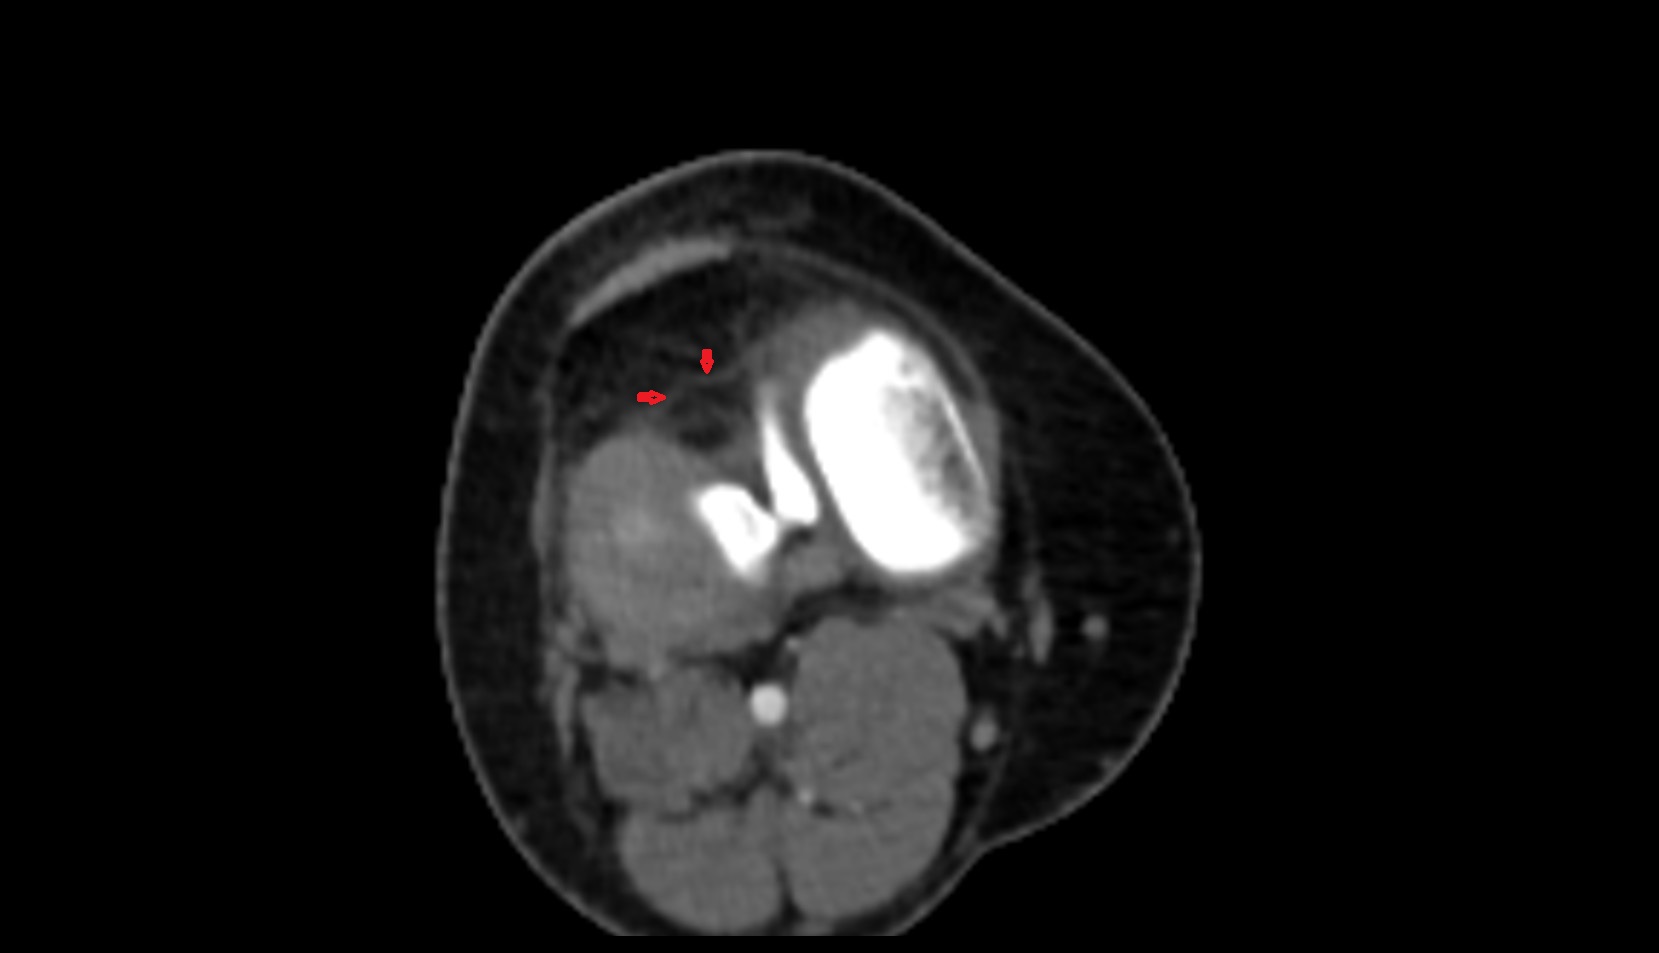

- Popliteal artery

- Popliteal vein

- Common fibular nerve

- Tibial nerve

- Knee Joint